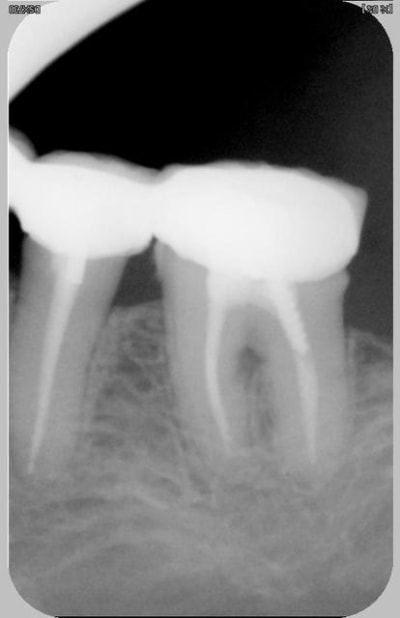

pour la radio 2 il y a une carie proximale mésiale au niveau radiculaire

La deuxième,elle a tout pour plaire quand même

le probleme de la 2eme pourrait etre l'egression par manque d'antagoniste par exemple

consequence rupture du point de contact et précarie mesiale associé à une prélesion interadiculaire et à une hypersensibilité radiculairedentinaire mesiale liee à la rupture du point de contact mesial

a mon avis il y a carie .point!,qui agrave surement encore le problème paro,ou bien provoquée par le problème paro,mais le résultat final est là,pas si obscur comme diagnostic!

L’égression d’une dent se fait normalement avec son parodonte (c’est le principe même de l’orthodontie), une simple égression ne peut donc pas expliquer la perte osseuse de ce cas n°2.

perte osseuse ou pas il y a bien une carie ...

et c'est ce qui motive la consultation

Par contre je pense que egression plus rupture du point de contact est souvent à l'origine d'une telle image

la carie sur la 2ieme photo atteind la moitier dentinaire, ce n'est pas une lesion débutante, donc il n'y a pas de reminéralisation possible